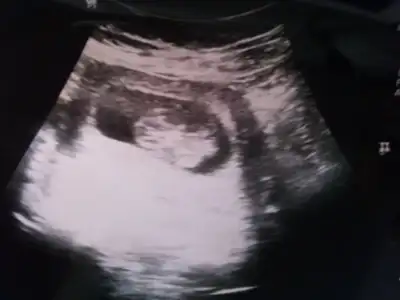

dr soylemeden siz gorun genital nub teorisi ( bebegin cinsiyeti)

Senin bebisinde erkek bence ama biraz daha net fotosu varsa bakabilirim evet dokrorlar anlıyorlar en başından ama soylemiyor lar ben oglumu 25 hftlk ken erkek oldugunu ogrendim hep kizdi ama kendim uyguladigim testler erkek oldugunu gösteriyor du bi tek dk kız diyodu 4 boyutu usg de anladi simdi ikinciye gebeyim bütün belirtiler kız dk kıza benziyor diyor ama net bi şey demiyorlar ama ben eminim icimde bir kız tasidigimdan bakalim hayirlisi canim

cnm nolur bunada bak erkekmi kızmı çok merak ettim şimdi....

cnm birde kese şeklinden anlayanlar var yuvarlaksa kız fasulye şeklindeyse erkek diyorlar tabi doğruluğu ne derece bilemiyorum....